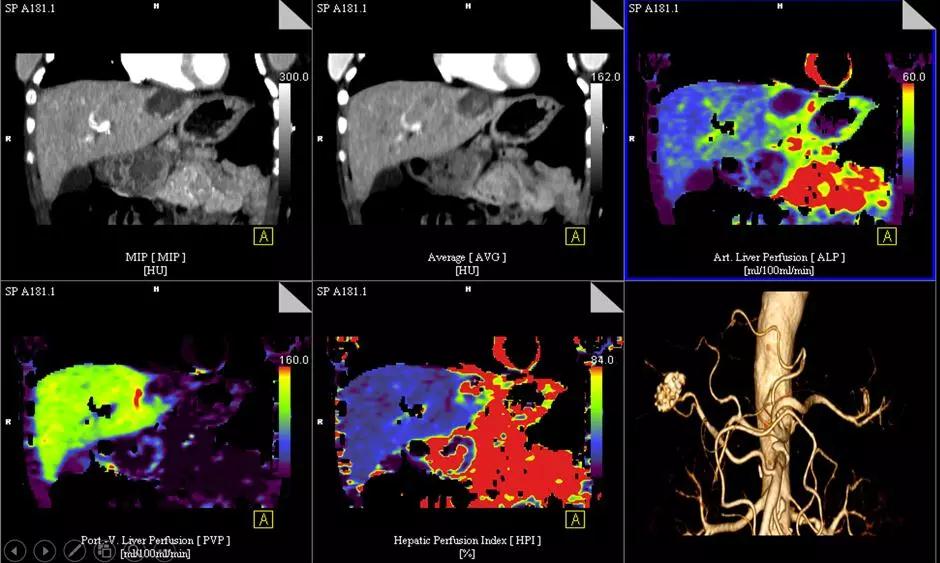

6.低劑量全臟器灌注和動態血流成像:

超大范圍80厘米功能成像,只需要一次平掃的輻射劑量,既可完成一站式全器官灌注掃描(神經、體部、心肌)和動態血流評估,更安全而全面的獲取形態學和功能學信息。

△肝臟5D灌注,本底輻射劑量,取代傳統多期相掃描